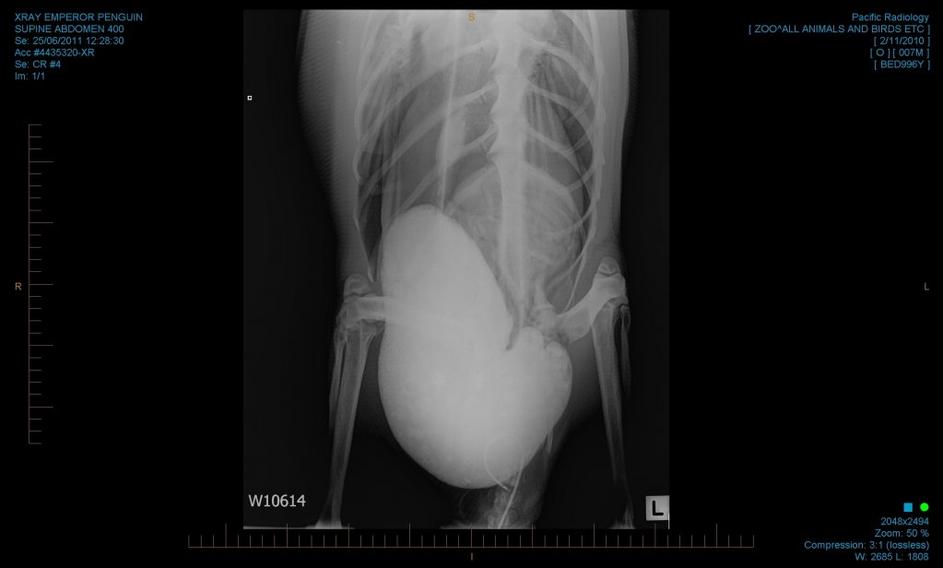

Strokovnjaki so kmalu po prihodu pingvina, ki so mu nadeli vzdevek "Vesele nogice", postali zaskrbljeni, saj se je njegovo zdravstveno stanje naglo poslabšalo, bil je dehidriran in izmučen. EPA

pingvin, operacija, Nova Zelandija, endoskopija "Pingvin bi moral v tem letnem času sedeti na morskem ledu na Antarktiki v 24-urni temi, " je ob prihodu cesarskega pingvina 3000 kilometrov od njegovega doma dejal predstavnik lokalnih oblasti za zaščito živali Peter Simpson iz Nove Zelandije. EPA

pingvin, operacija, Nova Zelandija, endoskopija Na Novi Zelandiji so doslej samo enkrat opazili cesarskega pingvina, in sicer leta 1967 na južnih obalah države. Živali z Antarktike sicer občasno zaidejo na obale Nove Zelandije, a razlog, zakaj je omenjeni pingvin opravil tako dolgo pot s svojega doma, ni znan. EPA